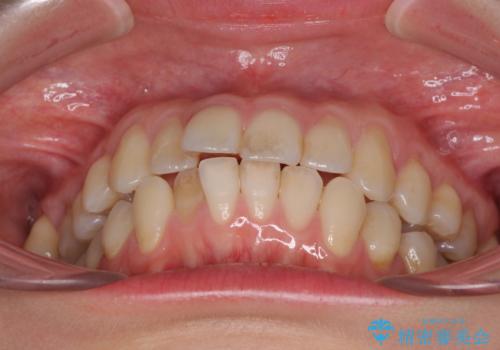

- 上下前歯のデコボコを気にして来院された患者様です。

インビザラインによる上下歯列の側方拡大と後方移動、IPR(歯と歯の間を削る)にるスペースの獲得により歯列を整えることとしました。